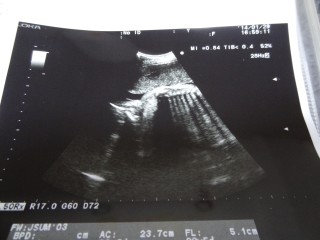

体重1245グラム。やや小さめらしいが健康の範囲で経過も良好!逆子の心配なくちゃんと頭位だった☆エコー写真はいいの撮れなくて背骨の写真だけ^^:

お尻の下から、撮ったエコーです。

おまたを開けています。

先生から100% 男の子と言われました(*^◯^*)